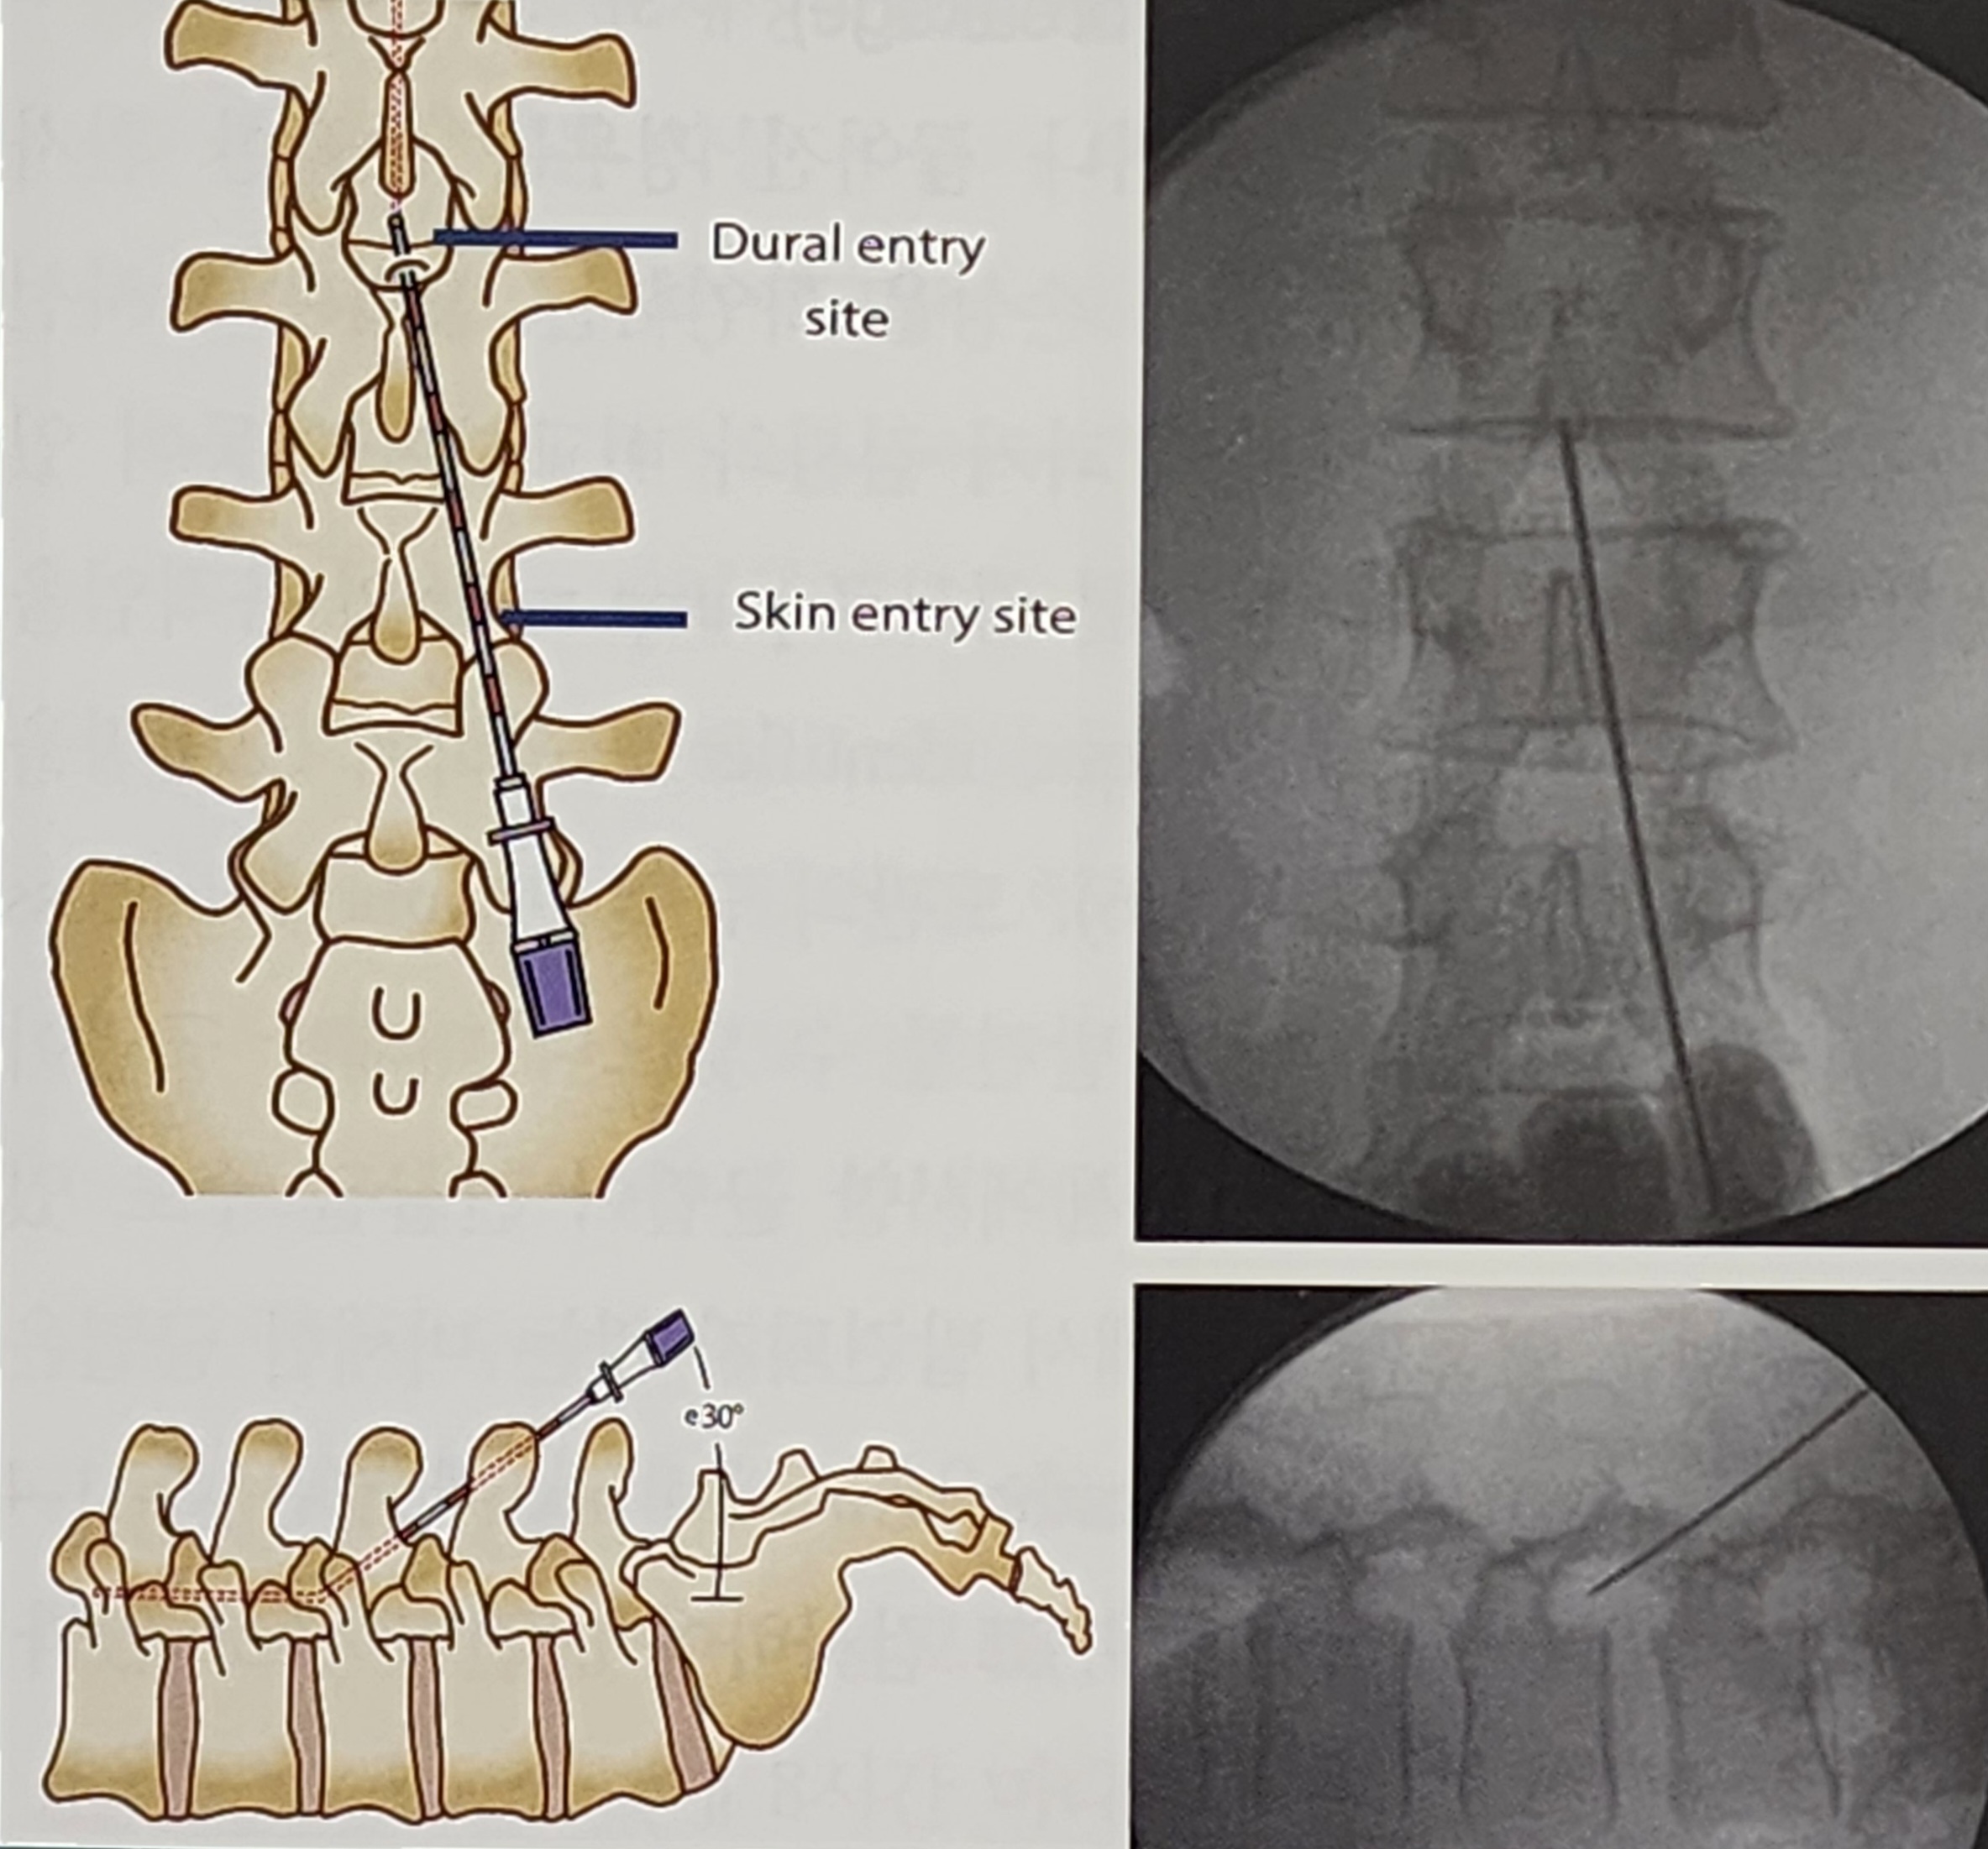

② 단회 주입 시험(Single-Shot Test, Screening Trial)

경막내 바클로펜이 효과적인지 판단하기 위해, 일회성(test dose)으로 약물을 주입하는 검사를 시행한다.

- 바클로펜 25~100μg을 척수강 내 투여

- 4~8시간 동안 효과를 관찰

- 근긴장도의 변화를 평가

- 부작용(저혈압, 호흡 억제 등) 발생 여부 확인

→ 긍정적인 반응이 나타나면 정식 펌프 삽입 고려